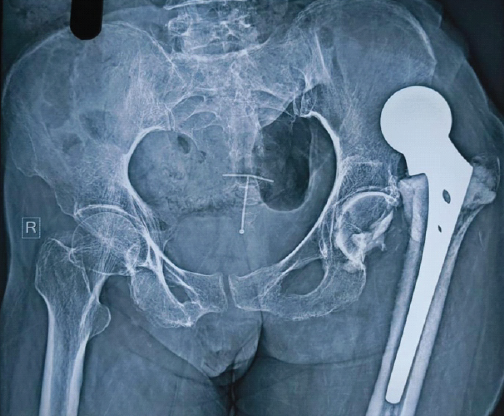

The Price of Poor Cementing: A Case Report On Chronic Hip Dislocation And Revision

Vasavi Pushadapu , Srikanth Sriramozu , V Sahetya Mohan Rao , Sreekalyani Kothapally